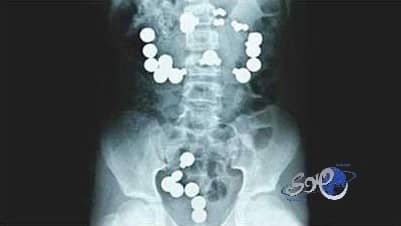

فوجئ أطباء روس عندما اكتشفوا أن طفلاً رضيعاً يبلغ من العمر عاماً واحداً قد ابتلغ 42 مغناطيسا من النوع الذي يستخدم عادة لتثبيت الأشياء على الأبواب الخارجية للثلاجات.

الأطباء العاملون في مستشفى تشيليا بينسك قالوا إن أم الطفل هرعت به إلى المستشفى وهي مذعورة بعد أن اكتشفت اختفاء قطع المغناطيس وظهور أعراض التوعك على رضيعها. ونقلت صحيفة روسية عن ناطق رسمي باسم المستشفى قوله: «كشفت صور الأشعة السينية عن وجود عشرات من الأجسام المعدنية الدائرية في داخل أحشاء الرضيع»، مشيراً إلى أن الأطباء نجحوا من خلال إجراءات طارئة في استخراج الأجسام الغريبة التي ابتلعها الصغير. وتعليقاً على ذلك قال رئيس قسم الجراحة في المستشفى «سبق لي أن استخرجت أجساماً غريبة من أحشاء مرضى في السابق، لكن هذا الرضيع حطم جميع الأرقام القياسية».